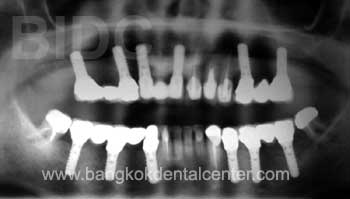

การรักษาด้วยรากฟันเทียม และใส่ฟันแบบติดแน่น

ปัญหาของคนไข้ : ใส่่ฟันปลอมแล้วเจ็บ รำคาญ ไม่กล้าสนทนา ไม่มั่นใจ

การรักษา : 24 ครอบฟัน และ 12 รากฟันเทียม

คนไข้มาจากประเทศ : รัสเซีย

ทันตแพทย์ : ทันตแพทย์สาขาทันตกรรมรากเทียม และทันตกรรมประดิษฐ์